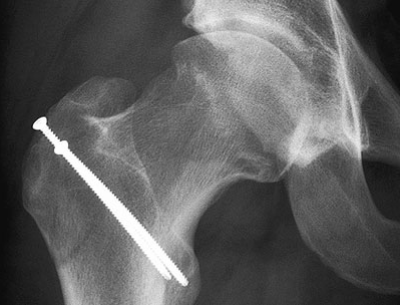

Von zentraler Bedeutung bei der Behandlung ist das Aufklärungsgespräch zwischen Arzt und Patient. Der Patient soll das anatomische Problem und die zu erwartenden natürlichen Folgen verstehen. Bei einem operativen Vorgehen ist es ausserordentlich wichtig, dass er eine realistische Vorstellung von dem zu erwartenden Operationsresultat hat. Insbesondere bei bereits fortgeschrittener Gelenkabnützung ist die Prognose ungewiss. Das operative gelenkerhaltende Vorgehen, welches wir in dieser Situation vorschlagen, ist die chirurgische Hüftgelenk(sub)luxation mit Entfernung der mechanisch störenden oder bereits zerstörten Gelenkanteile. Durch einen an der Hüftaussenseite angelegten Hautschnitt von etwa 25 cm Länge wird das Hüftgelenk eröffnet und der Hüftkopf so weit ausgerenkt, dass sämtliche betroffenen Gelenkstrukturen erkennbar und zugänglich sind. Dabei soll die umgebende Muskulatur geschont und die arterielle Durchblutung möglichst nicht beeinträchtigt werden. Zu stark überragende vordere Pfannenanteile werden mit dem Meissel abgetragen. Defekte Anteile an der Gelenklippe oder des angrenzenden Gelenkknorpels werden entfernt oder angenäht. Knochenauflagerungen am Übergang von Schenkelhals zu Hüftkopf werden stets entfernt, so dass dieser Übergang zusätzlich vertieft wird (Wiederherstellung einer genügenden Schenkelhalstaillierung). Bereits während der Operation lässt sich die verbesserte Beweglichkeit der Hüfte überprüfenn (Abb. 4).

Der Eingriff ist relativ komplikationsarm. In seltenen Fällen kann es zu einer Durchblutungsstörung des Hüftkopfes sowie zu einem Nicht-Anheilen der Knochenschuppe kommen, mit der die seitlichen Hüftmuskeln schonend weggeklappt werden und welche danach wieder an ihrer ursprünglichen Stelle mit Schrauben fixiert wird. Bis zur Beschwerdefreiheit kann es ein Jahr dauern. Bei einzelnen Patienten können geringe Restbeschwerden zurückbleiben. Zusammenfassend besteht beim Hüftimpingement ein Missverhältnis der Gelenkpartner im vorderen Gelenkabschnitt, wodurch verschiedene Strukturen irreparabel geschädigt werden und eine Früharthrose begünstigt wird. Durch einen operativen Rettungsversuch sollen die bestehenden Symptome behoben und vor allem ein weiteres Voranschreiten der Abnützungsprozesse vermieden werden. Inwieweit die Beschwerdefreiheit durch diese Operation auch längerfristig erreicht werden kann, wird sich erst in den nächsten 20 bis 30 Jahren weisen. Die regelmässige Nachkontrolle der bisher operierten Patienten ist deshalb von zentraler Bedeutung. Erst diese Langzeitverläufe werden zeigen, ob derartige operative Massnahmen ihren Stellenwert in der zukünftigen Orthopädie haben werden.